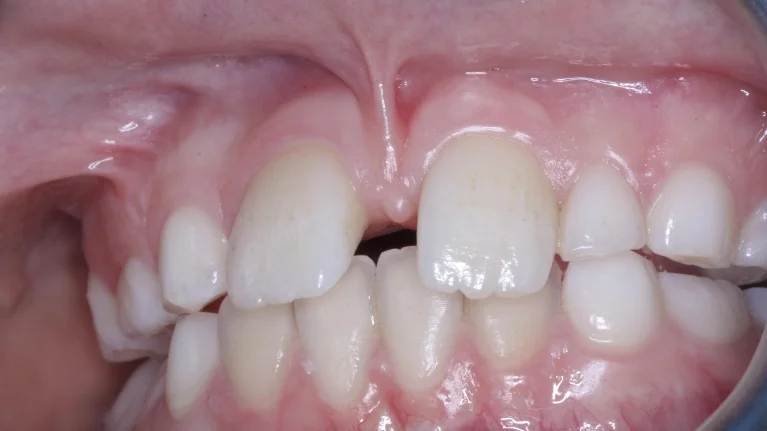

Wisdom teeth (third molars) are the last teeth to erupt in the mouth. Often, there isn't enough room in the jaw for them to grow properly, leading to impacted teeth that grow sideways or get trapped under the gums.

Impacted wisdom teeth can cause severe pain, swelling, infection, and damage to surrounding healthy teeth. Their removal requires precision and expertise to ensure a smooth recovery.